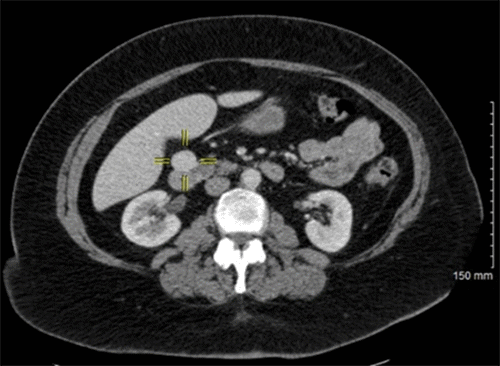

Additional biochemical workup came back normal, including alpha-fetoprotein (AFP), carcinoembryonic antigen (CEA), carbohydrate antigen (CA) 19-9, chromogranin A, serotonin, and 24-hour 5-hydroxyindoleacetic acid (5-HIAA). At this point, she was diagnosed with a nonfunctional pancreatic neuroendocrine tumor and proceeded with operative resection. While laparoscopic resection is a viable approach to specific pancreatic lesions, we decided to proceed with an open intervention to allow for manual palpation of the pancreas and the potential identification of any other small lesions that might have been previously missed. Upon intraoperative identification, the tumor was found to be solitary and resectable via enucleation, accomplished without incident (Figure 2). She tolerated the procedure well and was discharged home after an uneventful hospital course. Final pathology confirmed a well-differentiated neuroendocrine tumor, 3 cm in maximum dimension with negative margins.

Figure 2. Intraoperative Photo of Nonfunctional Neuroendocrine Tumor of Pancreatic Head. Published with Permission

Image obtained just prior to resection via enucleation